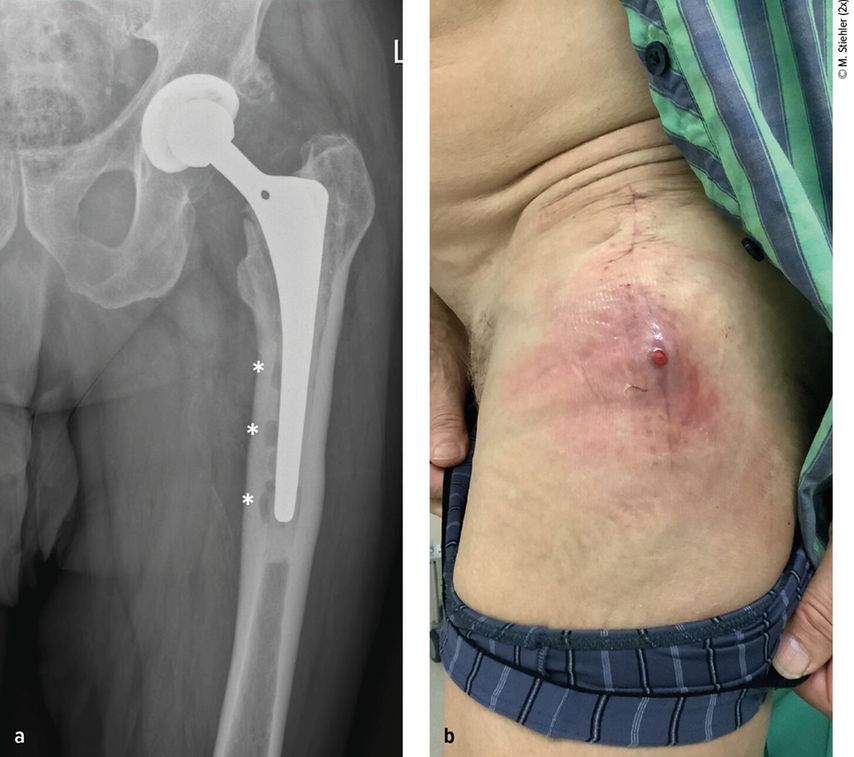

Angeborene Fehlstellungen des Unterschenkels

Kongenitale Deformitäten des Unterschenkels gehören zu den seltenen, aber medizinisch bedeutenden und operativ herausfordernden Diagnosen der Kinderorthopädie. Eine differenzierte ...